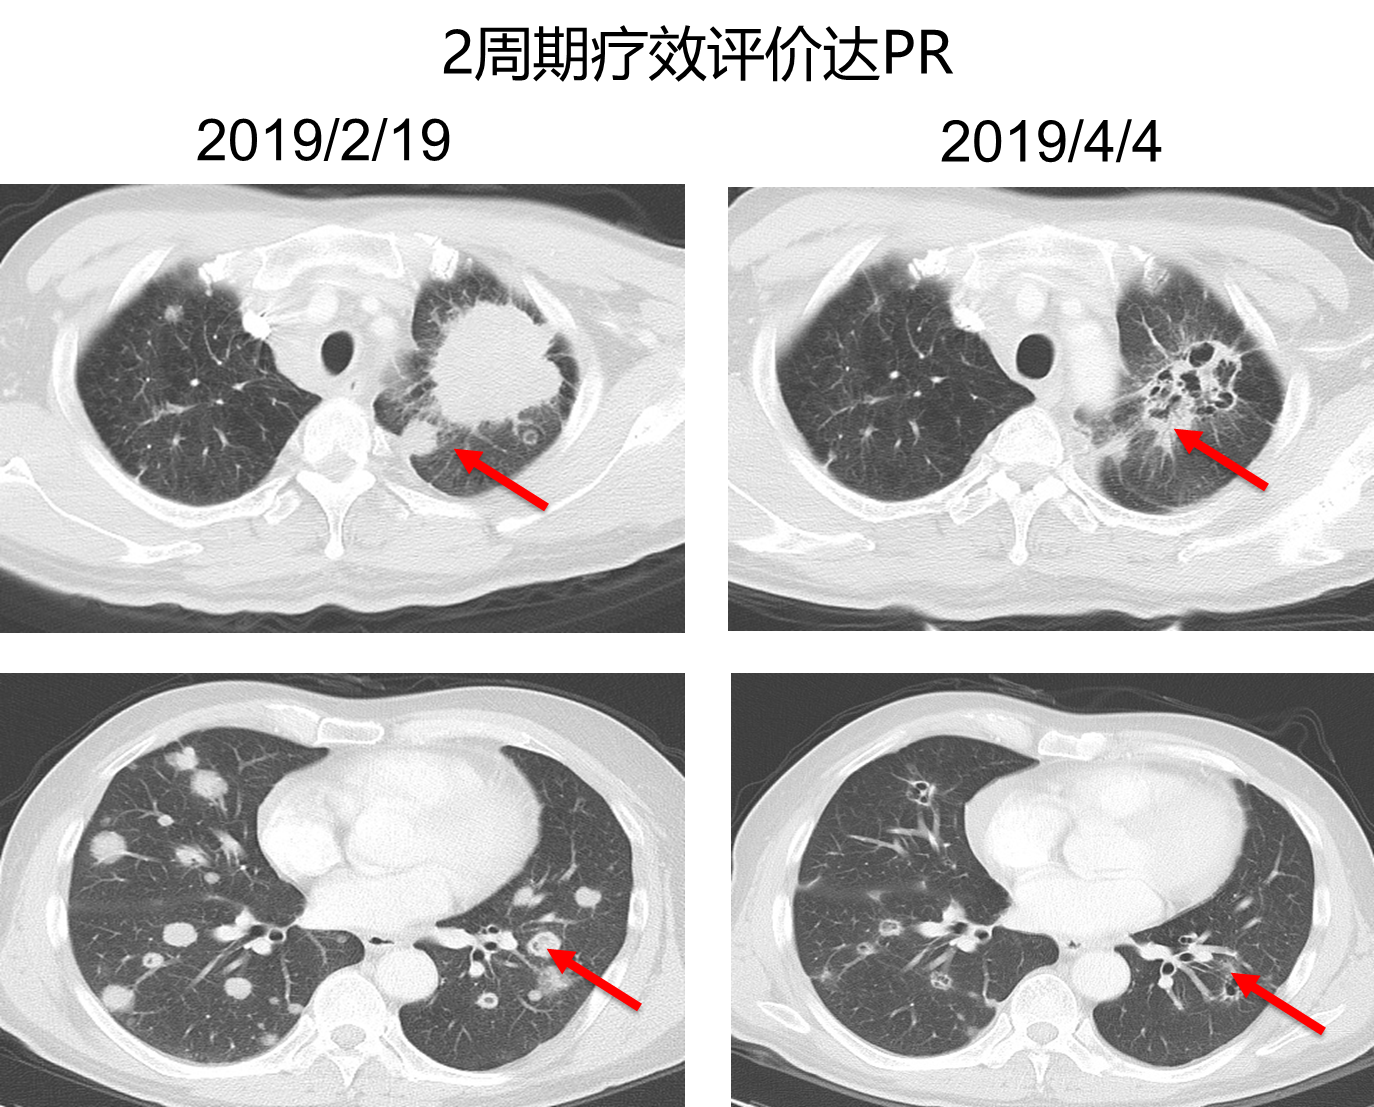

与患者沟通后,综合考虑疗效和性价比,二线治疗选择化疗+免疫治疗,具体方案为:白蛋白紫杉醇 200mg d1、d8+顺铂 40mg d1-3、信迪利单抗200mg d1,q3w,治疗2个周期后,复查胸部强化CT,病灶明显缩小,疗效评价结果为PR。治疗4个周期后,复查胸部CT,病灶继续缩小,疗效评价结果为维持PR。目前患者已经取得疾病缓解7.5月。

图3. 二线化疗+信迪利单抗治疗2周期后复查